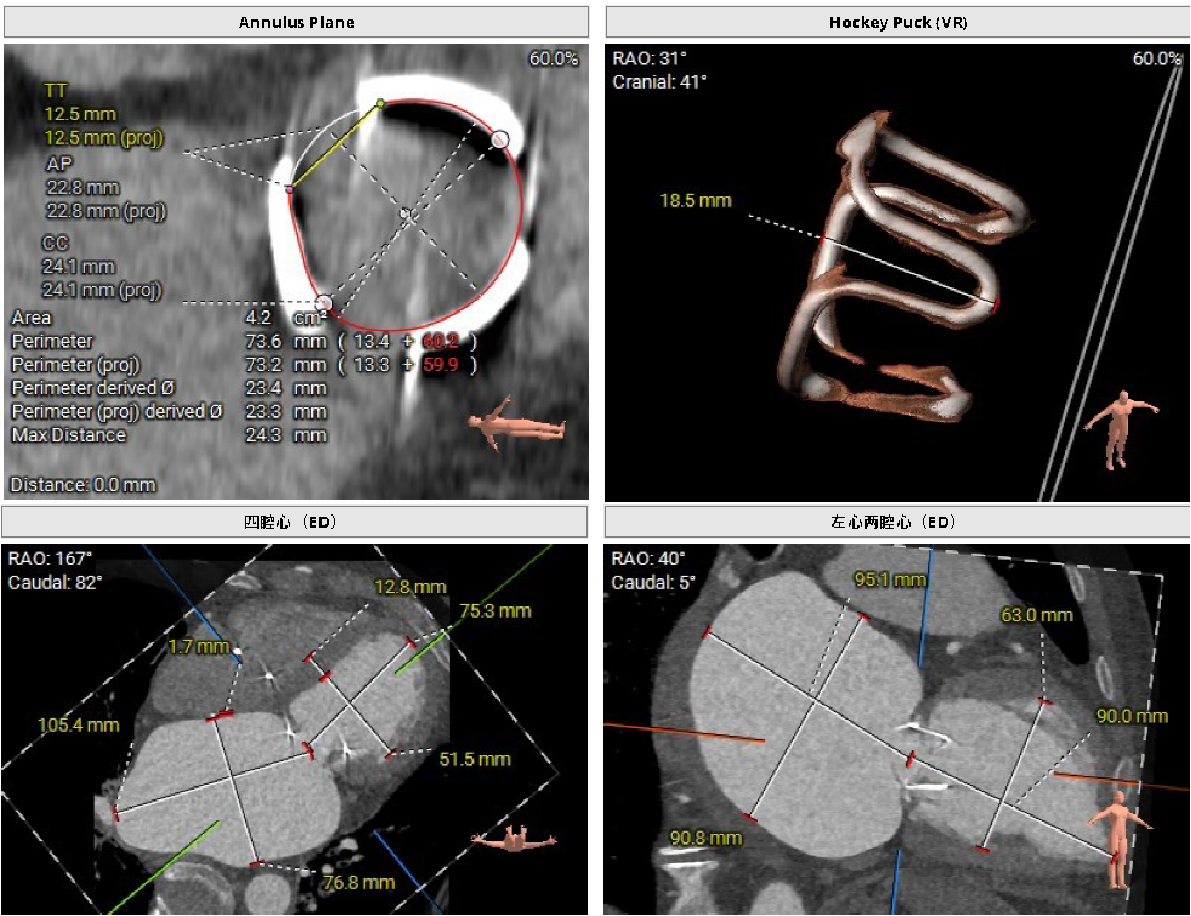

CT二尖瓣结构分析

可难题摆在眼前:第三次开胸换瓣手术,在医学领域是“高危禁区”。相关研究数据显示,此类手术的死亡率超过30%,加上患者已72岁高龄,身体耐受度远不如年轻时,一旦选择开胸,极有可能无法挺过手术关。